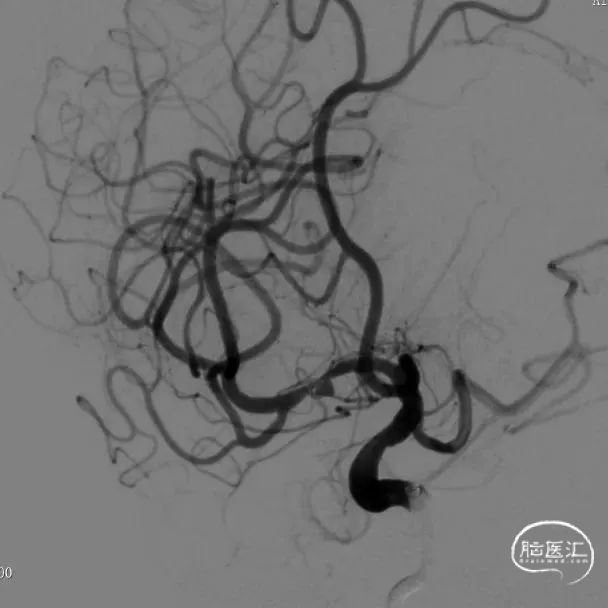

脑血管造影:右侧大脑中动脉M1段局部瘤样突起,远端重度狭窄,考虑右侧大脑中动脉M1段夹层动脉瘤。

右侧颈内动脉正侧位和右侧大脑中动脉工作位造影。

治疗之前3D和工作位(测量病变处近远端血管管径,M1近端1.9mm,M1远端1.7mm)。